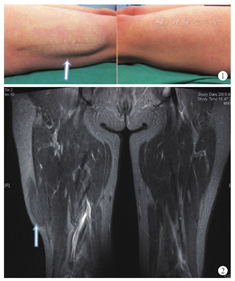

患者女,47岁,20年前外伤致右跟腱断裂,于当地医院取右大腿阔筋膜进行修补。术后右大腿逐渐出现局部包块,无明显疼痛,直立行走时增大,平卧后变小,移动度好,可向内推移,下肢无运动、感觉障碍。患者长期以来未就诊,但终因对右大腿外形不满意,于2015年6月就诊要求改善。体格检查:右大腿外侧可见约6 cm直线瘢痕,站立时右大腿外侧可见14 cm× 9 cm突起包块,触之表面光滑,质地柔软,移动度好,无压痛,听诊器听诊未闻及血管杂音,右髋屈曲放松后包块变小(图1)。右下肢活动无异常。MRI仰卧双腿自然伸直位检查:右大腿外侧股外侧肌形态饱满,体积较对侧增大,局部隆起,外侧方深筋膜不连续。T1WI及T2WI均与肌肉信号相似,T2WI脂肪抑制序列信号略偏高。后下部肌间隙模糊不清,后方筋膜不连续(图2)。诊断:右大腿股外侧肌疝(可复性)。